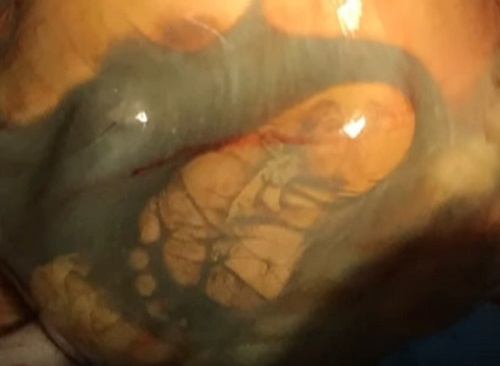

Ngay sau đó, các bác sĩ đã lập tức chuẩn bị tiến hành phẫu thuật cho người phụ nữ này. Với ca sinh mổ có nguy cơ cao này, 10 bác sĩ đã được huy động tham gia phẫu thuật.

Khi các bác sĩ xé bọc ối từ bụng người mẹ, họ còn chứng kiến một điều kỳ diệu hơn. Em bé không chỉ đang hít thở, mà còn phát triển đầy đủ, khỏe mạnh và có cân nặng 4,1 kg. Tỷ lệ sống sót của em là 1 trong 625 triệu. Trường hợp này thực sự là hi hữu.

| Đứa bé đã sống sót và chào đời kỳ diệu |

Người mẹ này sau đó đã đặt tên cho con gái mình là Veronika (có ý nghĩa là người chiến thắng).